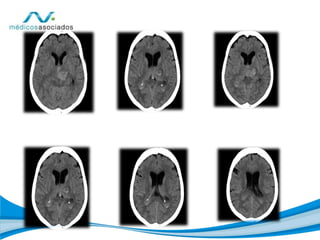

• TAC CEREBRAL SIMPLE

DETERIORO DEL GLASGOW, CON SOMNOLENCIA, RESPUESTA AL

ESTIMULO VERBAL FUERTE, NO SIGNOS DE FOCALIZACION, TAC

CEREBRAL, QUE EVIDENCIA ZONA DE HEMORRAGIA

INTRAPARENQUIMATOSA GANGLIO BASAL, QUE DRENA A

VENTRICULOS, CON AUMENTO DEL VOLUMEN DE LOS

VENTRICULOS, SIN DESVIACION DE LINEA MEDIA. NO DISMINUCION